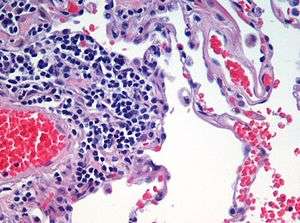

H&E stain

Hematoxylin and eosin stain or haematoxylin and eosin stain (H&E stain or HE stain) is one of the principal stains in histology. It is the most widely used stain in medical diagnosis and is often the gold standard; for example when a pathologist looks at a biopsy of a suspected cancer, the histological section is likely to be stained with H&E and termed "H&E section", "H+E section", or "HE section". A combination of hematoxylin and eosin, it produces blues, violets, and reds.

The staining method involves application of hemalum, a complex formed from aluminum ions and hematein (an oxidation product of hematoxylin). Hemalum colors nuclei of cells (and a few other objects, such as keratohyalin granules and calcified material) blue. The nuclear staining is followed by counterstaining with an aqueous or alcoholic solution of eosin Y, which colors eosinophilic structures in various shades of red, pink and orange.

The eosinophilic structures are generally composed of intracellular or extracellular protein. The Lewy bodies and Mallory bodies are examples of eosinophilic structures. Most of the cytoplasm is eosinophilic. Red blood cells are stained intensely red.

So, in optical microscopy we can observe :[1]

- Nuclei in blue/purple

- Basophils in purplish red

- Cytoplasm in red

- Muscles in dark red

- Erythrocytes in cherry red

- Collagen in pale pink